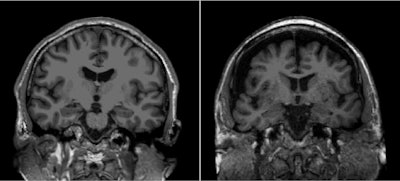

The authors noted that, at six-year follow-up, patients reporting social isolation via the Lubben scale had smaller hippocampus volumes and reduced cortical thickness on MR imaging. They also found that the higher the level of social isolation participants reported, the poorer their cognitive functions such as memory, processing speed, and executive capability.